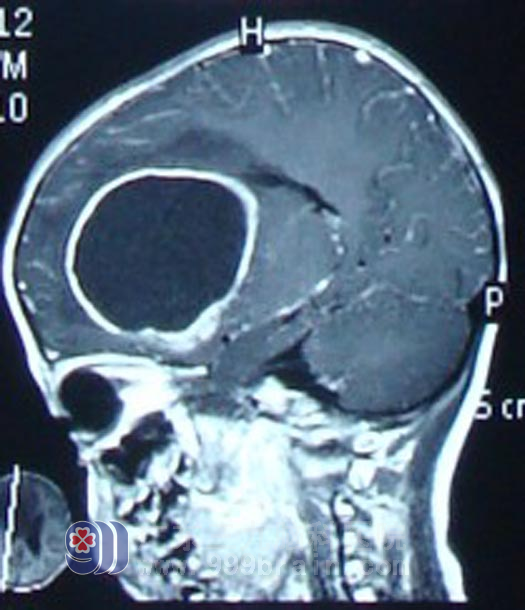

康康,5岁7个月,2011年1月开始出现反复头痛,呈进行性加重,当时未引起重视。

2月初出现呕吐,急入外院头颅CT检查示右额叶占位性病变,累及基底节区,周边钙化,内为低密度区,中线向左移位,左侧脑室扩大。来到广东三九脑科医院求医时,患儿精神状态极差。http://www.999brain.com/

术前